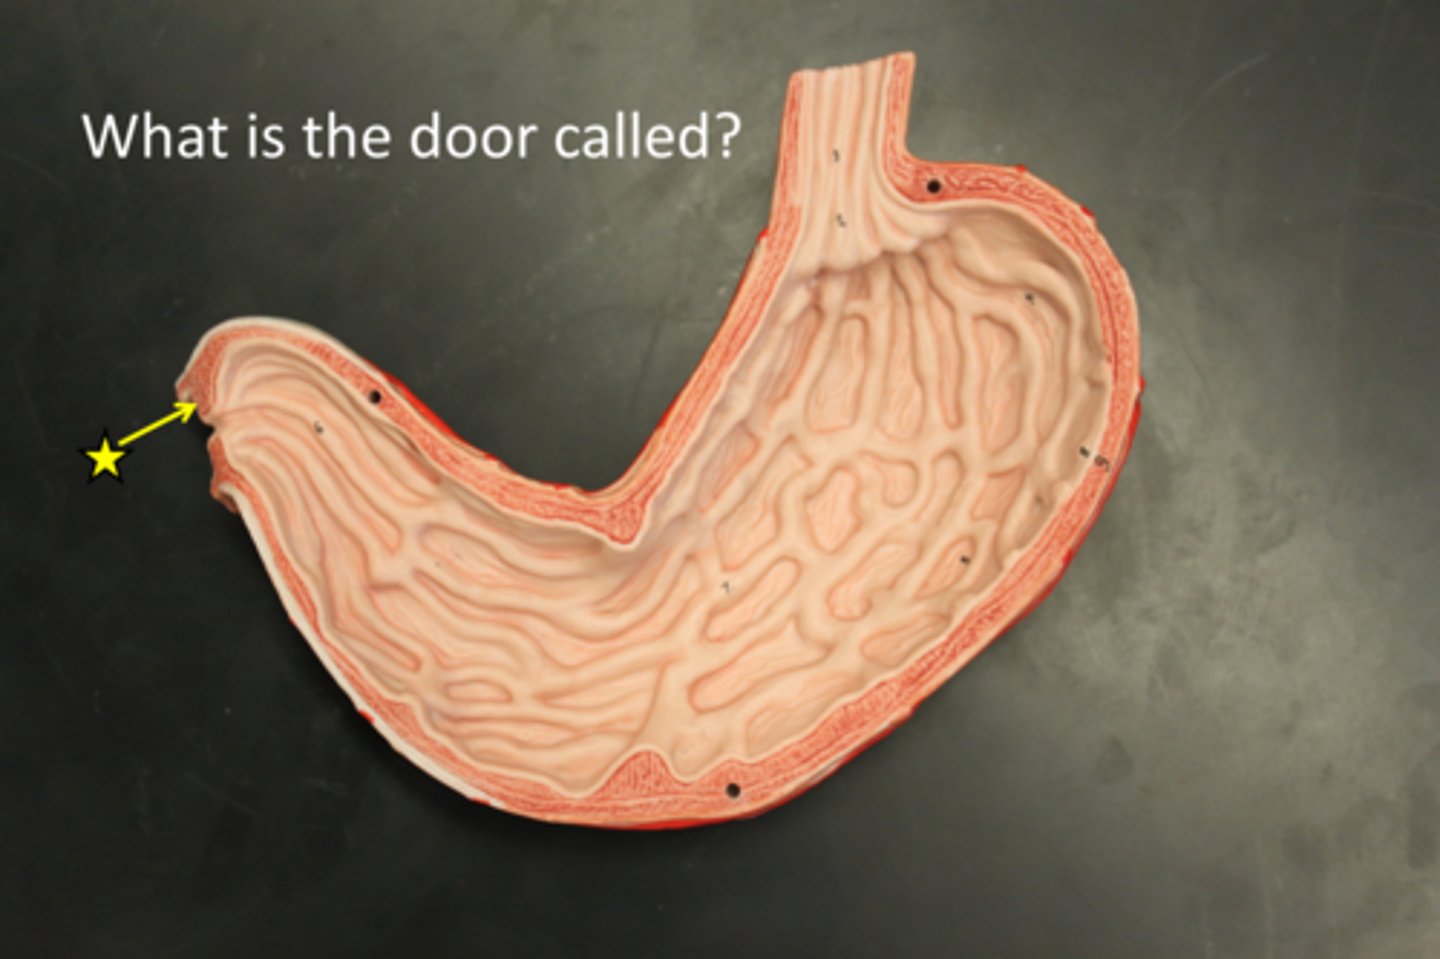

pyloric sphincter